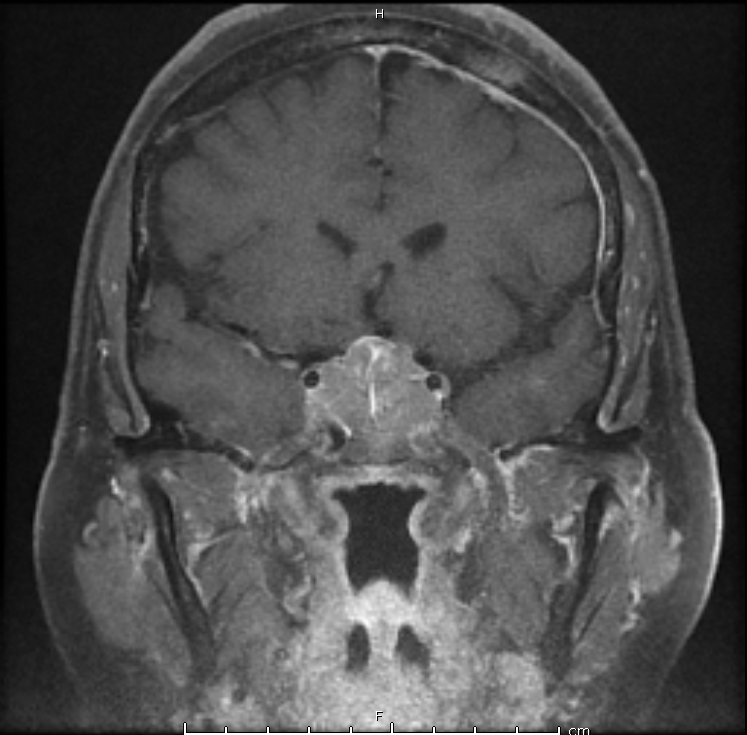

Case Presentation: A 54 year-old female presented to the ED with five days of fatigue, nausea, vomiting, and abdominal pain, increasing confusion, and somnolence after a recent viral illness. On physical exam, she was noted to have large, fixed masses in her breasts with bulky axillary lymphadenopathy. Upon further questioning, the patient revealed that she was diagnosed with breast cancer six years ago prior, but was told by her homeopathic provider that she was cured after her lumpectomy and that her existing breast masses were fibromas. CT scan revealed up to 4-cm enhancing masses in the bilateral adrenal glands. MRI brain revealed a 2.9cm mass invading the posterior pituitary stalk. Subsequent biopsy of a cervical lymph node revealed malignant breast cancer. Initial labs revealed hyponatremia, hypoglycemia, low AM cortisol, and low free T4 with inappropriately normal TSH. Patient was started on hydrocortisone and levothyroxine with improvement of her symptoms. On hospital day 4, the patient reported increased urination. Urine studies revealed immeasurably low urine osmolality and urine sodium, consistent with diabetes insipidus. Her polyuria resolved with initiation of desmopressin. Patient was eventually discharged home with desmopressin, levothyroxine, and hydrocortisone with plans to start chemotherapy and radiation therapy as an outpatient.

Discussion: Breast cancer is one of the most common cancers to metastasize to the pituitary. Metastases to to the pituitary frequently results in pan-hypopituitarism.